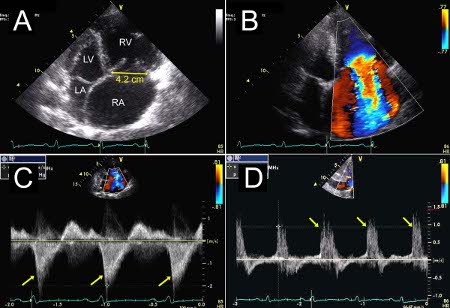

Severe tricuspid regurgitation due to annular enlargement. A. Systolic frame from apical 4 chamber view (Mayo Clinic display format with right ventricle on the right). Note tricuspid annular enlargement measuring 4.2 cm and tethering of the tricuspid leaflets leading to failure of coaptation of the tricuspid valve. B. Massive tricuspid regurgitation on Colour Doppler. C. Continuous Wave Doppler through the tricuspid valve. Note the dagger-shaped tricuspid regurgitant signal (arrows), consistent with rapid equalisation of pressures between right ventricle and right atrium, typical of massive tricuspid regurgitation. D. Pulsed Wave Doppler of the hepatic veins demonstrates late systolic flow reversals consistent with severe tricuspid regurgitation.

From the collection of Sorin V. Pislaru, Mayo Clinic